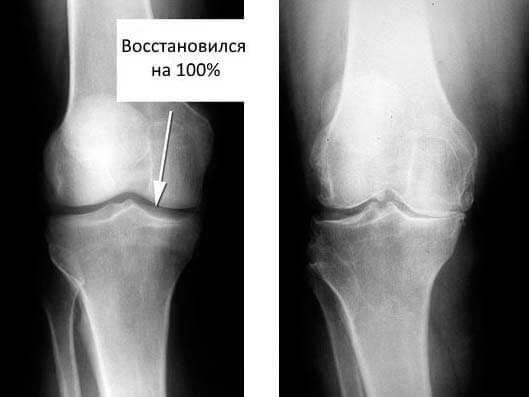

5 месяцев: сдала анализы и сделала рентген. Никаких

следов артроза! Хрящи в суставах как у 20-ти летней

девчонки. Докторша сказала, что на предыдущем рентгене скорее всего

был дефект, поэтому диагноз артроз был ошибочным.